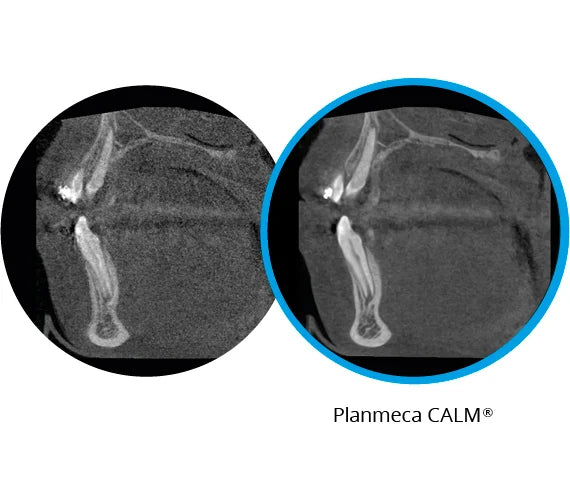

Corrección automática de los movimientos del paciente

Como la primera solución destinada al usuario final para la corrección del movimiento del paciente en el sector, el algoritmo Planmeca CALM™ no solo ahorra tiempo a los profesionales clínicos, sino que también protege a los pacientes de exposiciones innecesarias. Funciona con todos los tamaños de volumen y vóxel y solo agrega menos de 30 segundos al tiempo total de reconstrucción. El algoritmo está disponible como opción para todas nuestras unidades de procesamiento de imágenes dentales 3D.